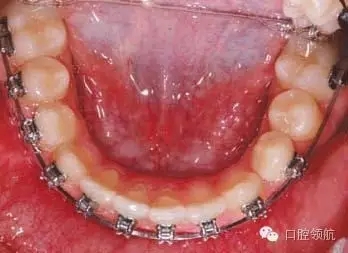

該病例建議的治療方案

治療目的應包括解除擁擠,排齊整平牙列,減小覆蓋,矯治異位阻生牙。應考慮排齊UR3,因其位置不佳,正畸治療難度加大,持續(xù)時間較長。另外,上牙列需要間隙解除擁擠,上切牙需要根舌向轉(zhuǎn)矩。尖牙是1/2牙尖的II類關系,因此要連同UL4考慮缺失的UL3以保持上中線。下牙弓應考慮拔除雙側(cè)前磨牙或第二磨牙。該病例決定拔除下頜第二磨牙。雖然拔除第二磨牙難度較大,但拔除下頜前磨牙會在排齊下牙列時產(chǎn)生過多間隙,影響長期治療。另外,需要較大支抗維持磨牙關系,糾正尖牙至I類關系。

拔除第二恒磨牙后可采用哪種矯治器促進下頜第二前磨牙萌出?

可能的選擇包括使用舌弓防止第一磨牙近中移動,或使用唇擋促進第一磨牙遠中移動并豎直。另外,可以在簡單的下頜固定矯治器上加推簧為第二前磨牙萌出開辟間隙。這種方法可能導致下切牙唇傾前移。這種情況下拔牙6個月后不要采取主動治療措施。豎直并遠中移動第一磨牙期間前磨牙會自動萌出。